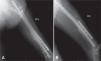

Todos los pacientes fueron llevados a cirugía bajo anestesia general o conductiva, colocando al paciente en posición de decúbito lateral. El procedimiento se inició retirando los tornillos de bloqueo distal o proximal para permitir compresión en el foco de no unión. En cuanto al foco de fractura, por la cara lateral del muslo, se realizó una incisión de 12 cm; al llegar al foco de fractura, se retiró todo el tejido fibroso y los fragmentos avasculares, y se comprobó la inestabilidad rotacional con un movimiento de rotación lateral y medial de la cadera. La fractura no consolidada fue fijada en una posición que permitiera las rotaciones normales comparadas con el lado contralateral sano. Se colocó la placa en la cara lateral del fémur, anterior o posterior según el espacio disponible para colocar tornillos de acuerdo con la radiografía lateral preoperatoria. Se escogió una placa de 8 a 10 agujeros de compresión dinámica estrecha para tornillos de cortical de 4,5mm; en algunos casos de osteoporosis marcada, se utilizó una placa bloqueada o una de 3,5mm, de acuerdo con la edad del paciente y el diámetro del hueso. Los 2 primeros tornillos, uno en cada fragmento óseo, se colocaron excéntricos y tomaron las 2 corticales (medial y lateral) para garantizar un efecto de compresión dinámica. Se utilizaron al menos 3 tornillos en cada fragmento, y se agregaron los injertos óseos alrededor del foco de fractura (figs. 1–4).

La cirugía de colocación de la placa antirrotatoria se realizó en promedio 14,5 meses después de la fractura (DS = 14,4), con una mediana de 10 meses y un rango entre 9 y 28 meses. Se usaron placas DCP de 4,5mm (94%) y de 3,5mm (6%). La fijación se hizo en promedio con 7 tornillos, 13 corticales, además de usar injertos óseos en el 92% de los casos. La única complicación que hubo después de esta cirugía fue la infección del sitio operatorio en un paciente (2%). A los seis meses del tratamiento de la pseudoartrosis con la cirugía de aumentación con placa antirrotatoria e injertos óseos autólogos, la consolidación fue completa en 44 fracturas (92%).